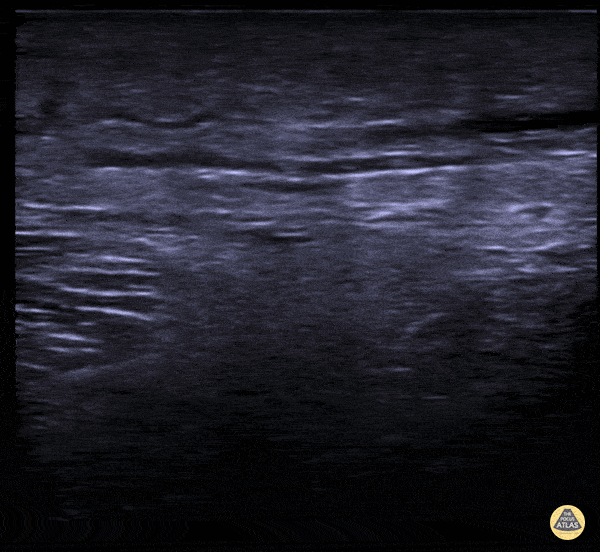

Soft Tissue - Subcutaneous Air in Necrotizing Fasciitis

A middle aged male presented to the ED for left leg pain after sustaining puncture wound to the foot 4 hours prior arrival. The ultrasound image demonstrates free air causing dirty shadowing seen deep to the fascial plane obscuring the normal muscle architecture in the middle of the screen. Nicmarie Maldonado, MD PGY-2; Eddie G. Rodriguez, MD; Miguel Agrait, MD; Michelle Surillo, MD - Division of Emergency Ultrasound, St. Luke's Medical Center/PHSU, Ponce, PR